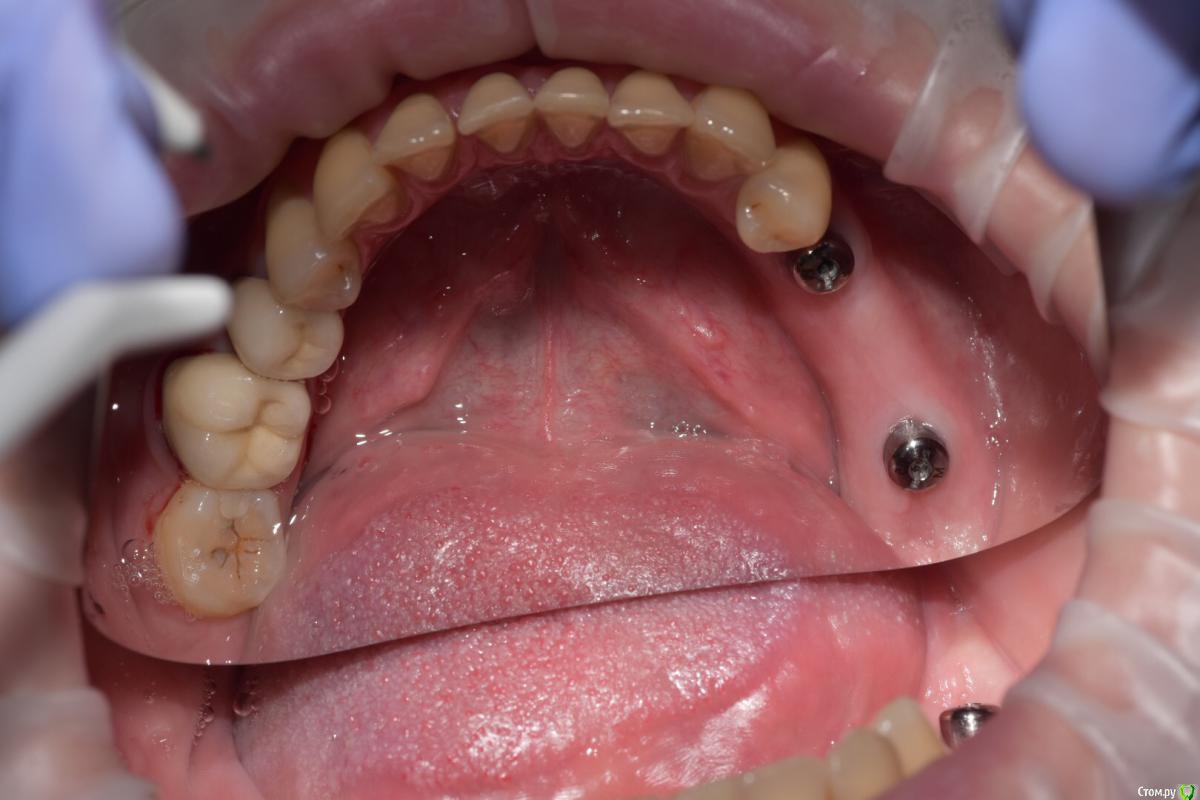

Santi Опубликовано 12 сентября, 2018 Поделиться Опубликовано 12 сентября, 2018 Коллеги, интересно мнение как бы вы поступили в аналогичной ситуации) Имеем Область забора и полученный ССТ Сразу после 2,5 мес пост оп 9 Ссылка на комментарий

Santi Опубликовано 15 октября, 2018 Автор Поделиться Опубликовано 15 октября, 2018 Результат после пары недель на времяшках. Доктора, если бы не делали ССТ получился бы такой профиль Пы Сы, биполярка залагала, работает только одна вспышка, за качество сорри )) 1 Ссылка на комментарий